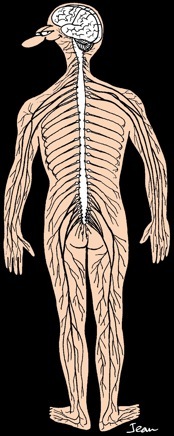

Chez tous les vertébrés, on distingue:

Le système nerveux central. Il est constitué de l'encéphale (cerveau et cervelet protégés par la boîte crânienne) et de la moelle épinière qui est logée dans la colonne vertébrale.

Le système nerveux périphérique (en noir) qui est formé des nerfs et ganglions).

le noyau

cerveau

cervelet

nerfs

moelle épinière

méninges

(3 membranes protectrices)

ganglion

matière grise

matière blanche

vertèbres